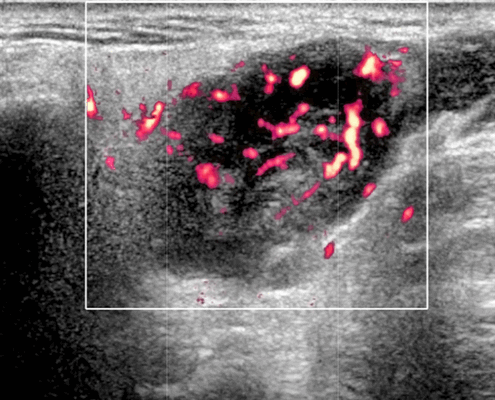

- Отмечается внутренняя васкуляризация на цветном доплеровском исследовании.

- Цветной допплер. Внутриузловая васкуляризация от умеренной до выраженной

Цветной допплер. Узловая НХЛ. Выраженная центральная или внутриузловая гиперваскуляризация. Паренхима при неходжкинской лимфоме более диффузная железистая гиперваскуляризация. Васкуляризация от умеренной до выраженной в плохо очерченных образованиях.